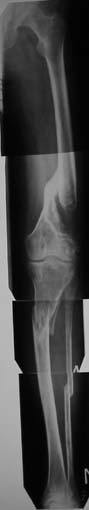

Вот и "клинический пример с отягощением", поступивший в минувшую пятницу:

Пациенту 42 года. Травма 4 года назад. "Мостик" на бедре вроде бы держит, но без брейса не ходит + постоянно костыли. Ко всему рубцы в области коленного сустава, качательные (3-5 гр.) в коленном и укорочение бедра 5 см, голени 1-1,5.

На этом ось практически не изменена, только укорочение.

Скорее соглашусь с Е.Чекашкиным, и для решения вопроса о плане лечения крайне необходимо четко представлять анатомо- топографические характеристики четырехглавой мышцы. ЭМГ нужна, но важнее контрастная рентгенография, поскольку при укорочении брюшка прямой и промежуточной мышц на 40% за счет атрофии и при наличии фиброзных изменений ( а они есть однозначно), любые операции по увеличению объема движений в коленном суставе практически бесполезны.Кроме того, необходимо четко представлять состояние праартикулярных тканей( УЗИ, КТ,МРТ)и кости в зоне консолидации (КТ)Кстати, брюшко не может быть" удлиненным по сравнению с укороченной костью", поскольку за 4 года ретракция и атрофия сделали свое дело. При сохранении достаточной длины и тлщины мышечного брюшка и хорошем состоянии параартикулярных тканей можно попытаться увеличить объем движений в суставе. В противном случае - удлинить бедро . На представленном снимке не совсем ясна ситуация в зоне консолидации.Насколько прочно сращение?

На рентгенограмме прямая и промежуточная мышцы больной с врожденным укорочением бедра на 7 см( для примера). Нормальная ситуация.